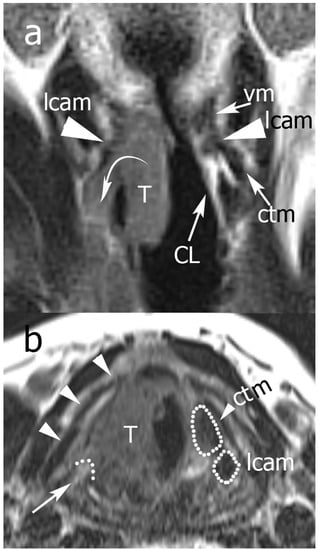

Figure 5.

Example of Pattern C. From top to bottom: (a) TSE-T2 on coronal plane; (b) TSE-T2 on axial plane. In (a) the right glottic-subglottic tumor infiltrates the inferior PGS (curved arrow) extending outside the larynx, the vocal and lateral cricoarytenoid muscles are partially infiltrated, and the cricoarytenoid muscle is completely undetectable because of invasion (the same muscles are normally visible on the left side). There is infiltration of the right cricoid lamina, although it is normal on the left side. In (b) the tumor infiltrates the lateral cricoarytenoid and cricothyroid muscles, visible on the left side. Arrowheads indicate the right thyroid lamina, which is not infiltrated. A curved dotted line and arrow indicate the posterior front of the neoplasm. Legend: CL, cricoid lamina; ctm, cricothyroid muscle; lcam, lateral cricoarytenoid muscle; T, tumor; vm, vocal muscle.